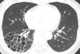

Honeycomb lung

Honeycombing or "honeycomb lung" is the radiological appearance seen with widespread fibrosis and is defined by the presence of small cystic spaces with irregularly thickened walls composed of fibrous tissue. Dilated and thickened terminal and respiratory bronchioles produce cystic airspaces, giving honeycomb appearance on chest x-ray. [Source: Wikipedia ]